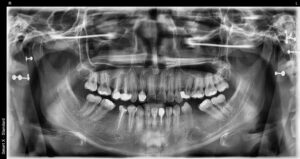

모든 치료가 마무리된

구강 내 사진과

파노라마 사진입니다.